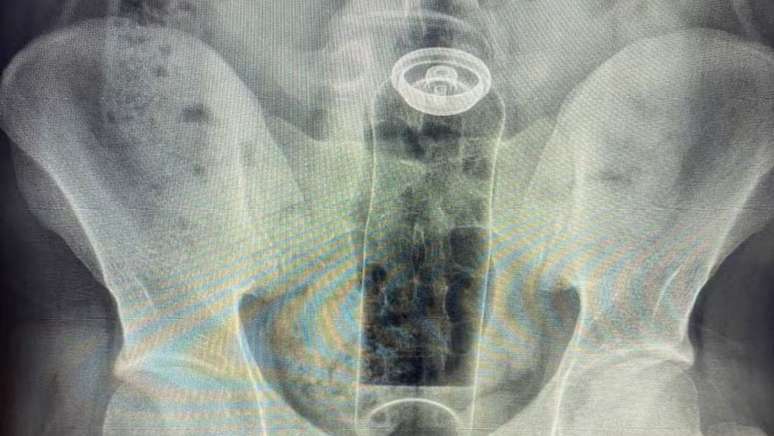

Paciente introduziu desodorante no reto e precisou de cirurgia para remover objeto

Foto: Reprodução/Arquivo pessoal